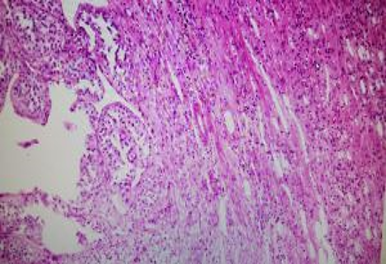

Fig shows an endoscopic biopsy from a 54 year old individual. Identify the anatomical part of the intestine. What is the pathology. With what clinical symptoms do these patients present? (see surface epithelium)

Ultrasonically guided fine needle aspiration cytology of a mass in front of the neck of a 40 year old female. Patient complained of severe back ache and had osteoporosis. Fig 1 and Fig 2 : are shown. Make your diagnosis.

Fig 1

Fig 2